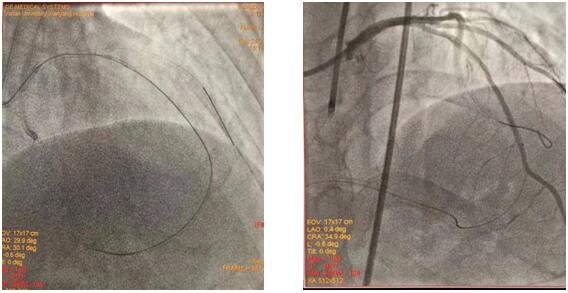

(插圖說明:圖1為雙側(cè)造影圖、圖2為導絲正向通過圖、圖3為求那邊、圖3為球囊通過圖、圖4為導絲逆向通過圖)

在吳棟梁院長的協(xié)調(diào)安排下,從12月24日清晨7:30到12月25日清晨7:50安全完成62例介入手術(shù)。其中,心血管內(nèi)科二病區(qū)介入團隊在左梅主任的帶領(lǐng)下,清晨七點半開始,C3830電極對于左束支區(qū)域起搏、永久起搏器的成功置入,逆向技術(shù)開通LAD近段無殘端閉塞病變的順利完成,創(chuàng)造著一個個生命的奇跡,為心血管病患者帶來一個不平凡的平安夜。